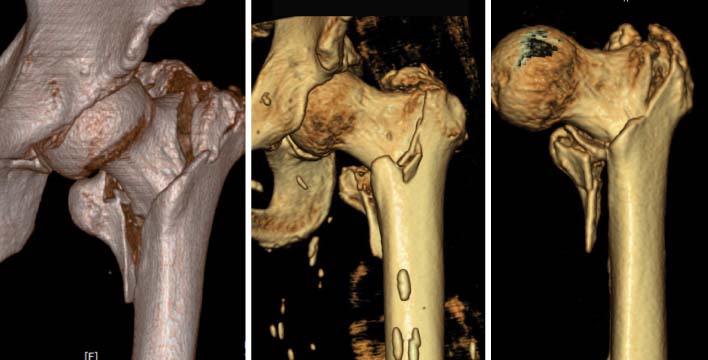

*Vertical distance from greater trochanter to fracture line. †Vertical distance from proximal boundary of lesser trochanter to fracture line. ‡The angle between the fracture line of the distal fragment and anatomical axis of the femur.